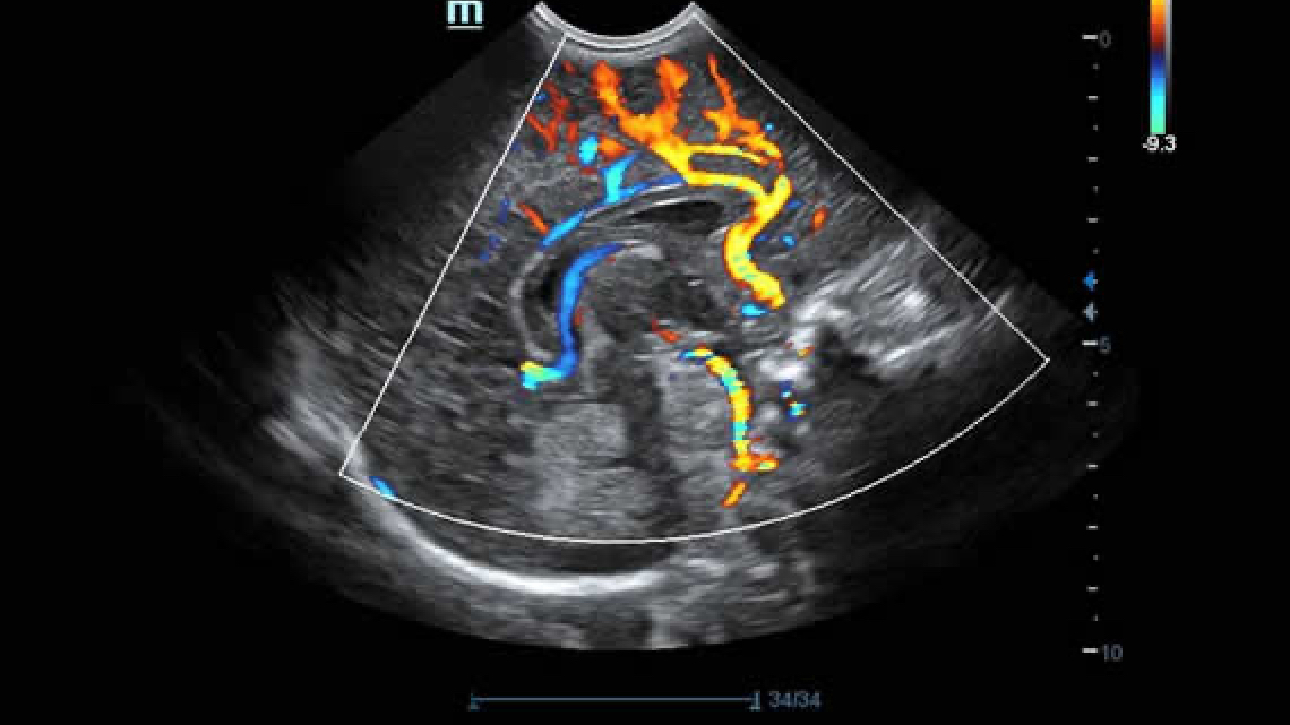

Clinical Images